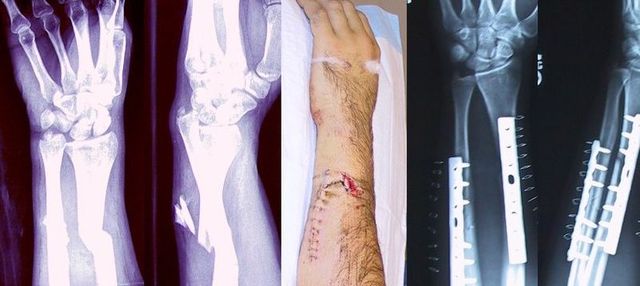

• I broke my arm

I was climbing a tree and all of a sudden the branch I was on broke, I plummeted and on the way down hit my arm on a branch. i had to go to the hospitable and i found out that i ghad shattered my whole arm and fractured my shoulder and my shoulder blade.